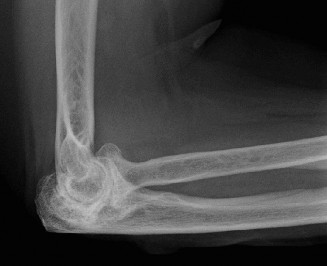

Treat a patient with infected total shoulder arthroplasty? CASE 21 A 70-year-old, right-hand-dominant female presents to clinic complaining of 4 years of gradually worsening chronic right shoulder pain and stiffness. She says the pain is worse at night and with any range of motion, denies a history of trauma, pain in other extremities, or numbness or tingling of the right upper extremity. She notes that her mother suffered from rheumatoid arthritis that affected her shoulder. Physical examination reveals decreased muscle bulk over the right supra- and infraspinatus fossae compared to the contralateral side, limited active and passive ROM, marked weakness with external rotation, and 4+/5 strength with shoulder abduction. X-rays of the right shoulder are shown in Figures 2–58 and 2–59.

Figure 2–58

Figure 2–59

The correct answer is (C). Rotator cuff tear arthropathy consists of a combination of rotator cuff insufficiency, glenohumeral joint degenerative changes, and superior humeral head migration. It is more common in women and also more often found on the dominant side. The patient’s clinical examination with weakened external

rotation and muscle atrophy signaling incompetent supra- and infraspinatus muscles point to rotator cuff insufficiency, and her plain films reveal narrowed glenohumeral joint space as well as superior migration of the humeral head. Choice D is incorrect because, while radiographs would show narrowing of the glenohumeral joint space, they would also likely show numerous osteophytes and posterior wear of the glenoid. Choice B is incorrect because, while adhesive capsulitis does present as decreased active and passive range of motion, the patient’s constellation of symptoms pointing towards rotator cuff insufficiency along with the radiographs make cuff tear arthropathy the more likely choice. Finally, Choice A is incorrect because even though she has a positive family history of rheumatoid arthritis, it is less likely to present only in a single joint. Also, rheumatoid arthritis on radiography appears more as an erosive process without the characteristic superior migration of the humeral head.

Which of the patient’s radiographic findings is most indicative of chronic rotator cuff insufficiency?

- Superior migration of the humeral head

The correct answer is (A). Superior migration of the humeral head would be most indicative of chronic rotator cuff insufficiency associated with cuff tear arthropathy, as it is a direct result of the inability of the rotator cuff tendons to help maintain the humerus in its normal position. Acetabularization of the undersurface of the acromion is commonly associated with superior migration of the humeral head found in rotator cuff tear arthropathy, and can be assessed using the Hamada classification, which is based on measurements of the acromiohumeral interval on radiography (Table 2–8). Choices B and C are incorrect because, while narrowed glenohumeral joint space and subchondral sclerosis are associated with rotator cuff arthropathy on radiographs, they indicate degenerative joint changes rather than chronic rotator cuff insufficiency. Choice D is incorrect because it is not a specific sign of rotator cuff arthropathy.